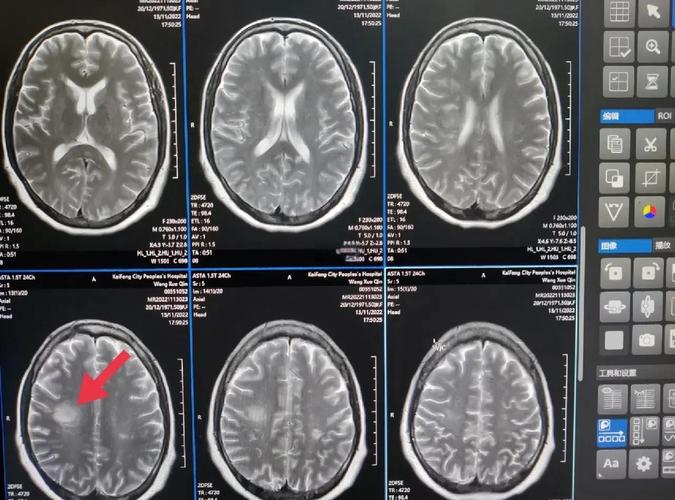

| CT / CTA | 脑组织结构 + 血管结构 | 快速、普及、能快速排除脑出血、CTA能清晰显示血管 | 急性期脑梗塞(6小时内)可能看不出来、有辐射、含碘造影剂有过敏风险 |

| MRI / MRA | 脑组织结构 + 血管结构 | 是目前诊断脑梗塞最敏感的检查,能最早发现坏死的脑组织、无辐射、MRA对血管显示清晰 | 费用高、检查时间长、幽闭恐惧症患者不适用、体内有某些金属植入物者禁用 |